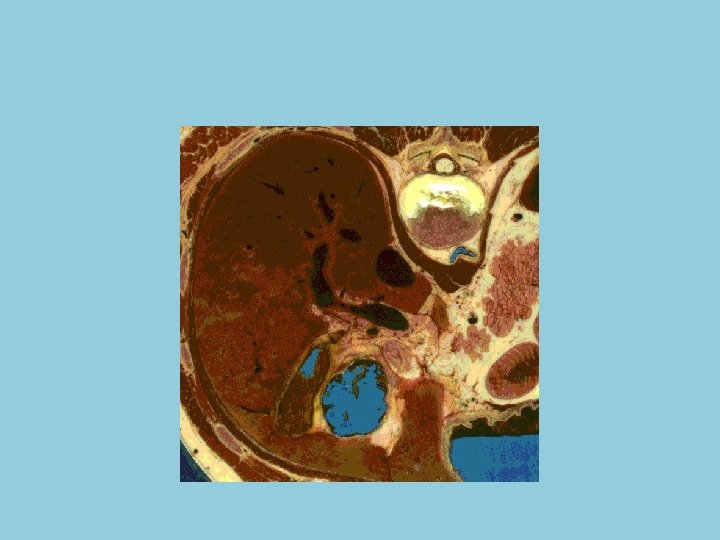

Couleur et consistance • Le foie est rouge brun. Il a une consistance assez ferme et cependant il est friable, fragile et se laisse déprimer par les organes voisins

Poids et dimensions • Le foie est l'organe le plus volumineux de l'organisme. Son poids est d'environ 1500 grammes sur le cadavre. Chez le vivant, le foie contient en plus 800 à 900 grammes de sang. Il mesure en moyenne 28 centimètres dans le sens transversal, 16 de haut et 8 d'épaisseur, dans la région la plus volumineuse du lobe droit.

Anatomie 1 • Le foie est un organe thoraco-abdominal. La majeure partie de cette glande est logée sous la très profonde coupole diaphragmatique droite qui sépare le foie du poumon droit et d'une partie du coeur. Il surplombe la partie droite des viscères abdominaux auxquels le relient d'une part des vaisseaux (veine porte et artère hépatique qui apportent le sang; veines sushépatiques qui en assurent le drainage) et d'autre part les voies biliaires qui permettent l'évacuation de la bile vers l'intestin.

L’apport sanguin • L’apport sanguin hépatique est double : • - par la veine porte qui draine le territoire splanchnique (veine splénique, veine mésentérique supérieure et veine mésentérique inférieure) et apporte les 2/3 du volume sanguin hépatique ; • - par l’artère hépatique issue du tronc coeliaque. • L’ensemble veine porte - artère hépatique constitue, avec le canal cholédoque, le pédicule hépatique. La ramification de ce pédicule permet d’isoler 7 segments (Figure 1) dont la connaissance est nécessaire pour la prise en charge radiologique, chirurgicale et anatomopathologique des pathologies tumorales.